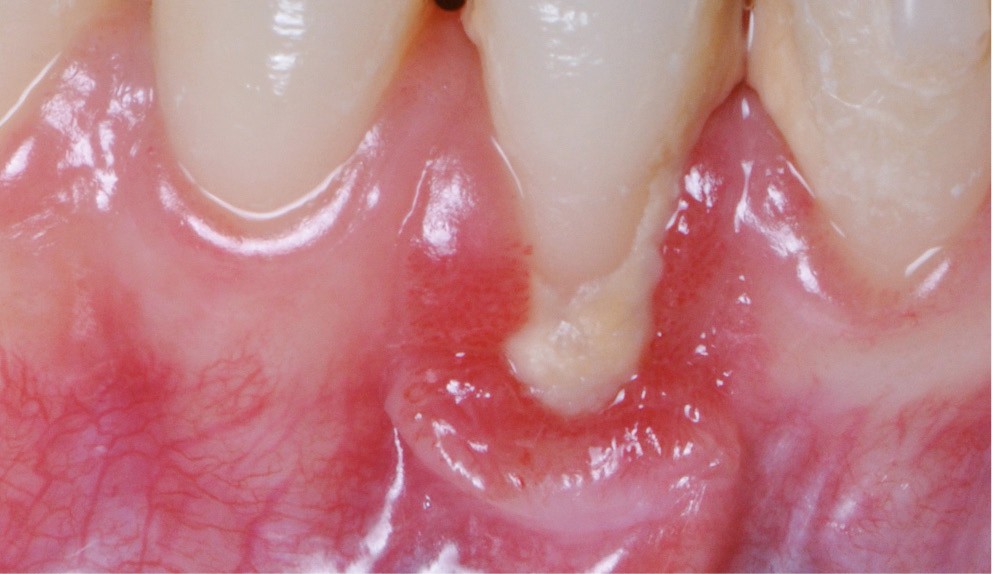

Zuchelli et coll. [1] définissent quatre causes à l’origine des récessions gingivales à la suite d’une déhiscence osseuse : les causes traumatiques (fig. 1) par le brossage, le surcontour prothétique, les piercings ; les causes bactériennes (fig. 2) liées à une inflammation marginale ; les causes virales par le virus de l’herpès simple ; et les origines mixtes, à savoir traumatiques et bactériennes (fig. 3). Le diagnostic de récession liée à la plaque dentaire dépend de la présence de dépôts tartriques et/ou d’inflammation des tissus environnant les zones exposées. En présence d’une origine mixte, la récession est d’abord initiée par un brossage traumatisant, rendant la surface radiculaire hypersensible ou irrégulière, ayant une répercussion négative sur le brossage et l’accessibilité à l’hygiène.